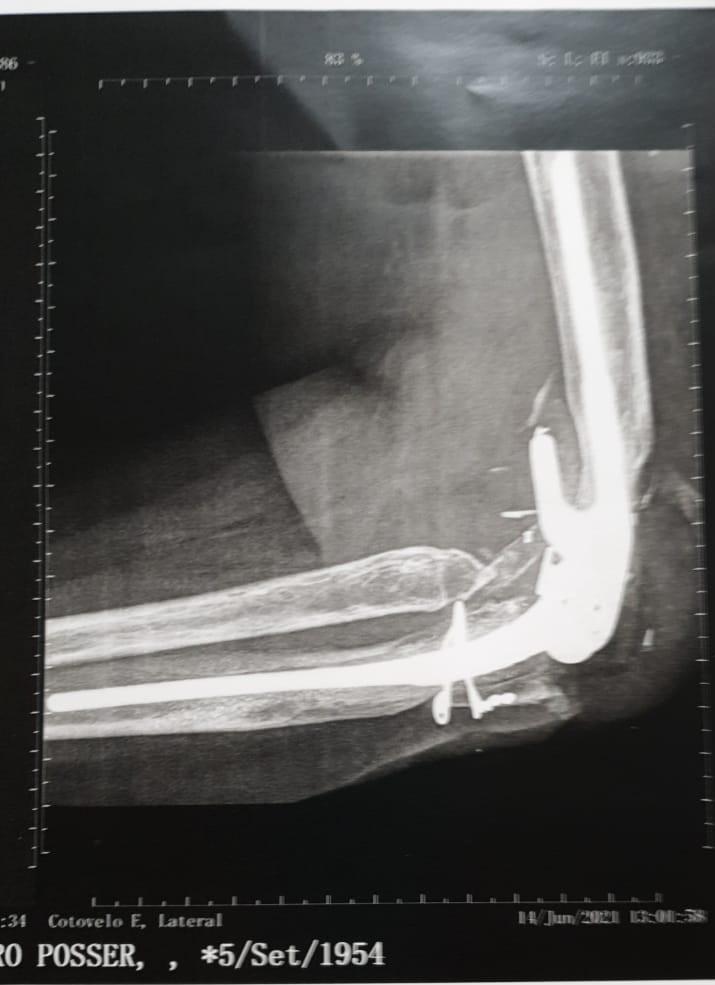

Depois de sofrer um grave acidente de carro em 2002, Salete Posser, de 66 anos, quase perdeu o braço esquerdo. Na época, a empresária de Primavera do Leste foi submetida à cirurgia de artroplastia total no cotovelo, que é a reconstrução da articulação mediante a utilização de prótese. Quase 20 anos após a primeira cirurgia, a paciente precisou realizar novamente o procedimento para substituição da prótese, que ocorreu no último dia 02 de setembro, no Hospital Santa Rosa, em Cuiabá.

Devido à complexidade deste tipo de cirurgia são poucos profissionais no país que realizam a artroplastia total no cotovelo. O primeiro procedimento de Mato Grosso foi o da empresária Salete, realizado em 2003, no Hospital Santa Rosa, em Cuiabá, por uma equipe que envolveu os médicos ortopedistas Marcelo Hide Matsumoto, referência nacional em cirurgias de membros superiores e cotovelo pela Escola Paulista de Medicina; e Maurício Allet, também especialista em cirurgia de mão e em reimplantes de membros, que atua desde 1999 em Mato Grosso com cirurgia de mão.

O segundo procedimento da empresária ocorreu mais recentemente, no início de setembro deste ano, e foi necessário devido ao desgaste natural dos componentes. Graças à prótese, Salete hoje tem uma vida normal, realizando todos os movimentos do braço e com sensibilidade em todos os dedos das mãos.

De acordo com Allet, é comum haver esses desgastes com o tempo. E para esta segunda cirurgia a equipe novamente contou com o médico Marcelo Matsumoto e com o chefe do grupo de Ombro e Cotovelo da residência do Hospital Santa Marcelina, de São Paulo, Anderson Uehara.

Maurício Allet explica que esse tipo de cirurgia é complexa, mas segura. Os materiais usados são de alta qualidade, material importado, de alta resistência.

Foram seis horas de cirurgia e além da substituição da prótese, onde colocamos um novo ‘cotovelo’, também tivemos que realizar a reconstrução de ligamentos, de músculos e colocar um enxerto ósseo, extraído do osso ilíaco (bacia). E novamente foi um sucesso, com a paciente se recuperando bem. Ela já mexeu o cotovelo no pós-operatório e está com a sensibilidade dos dedos da mão